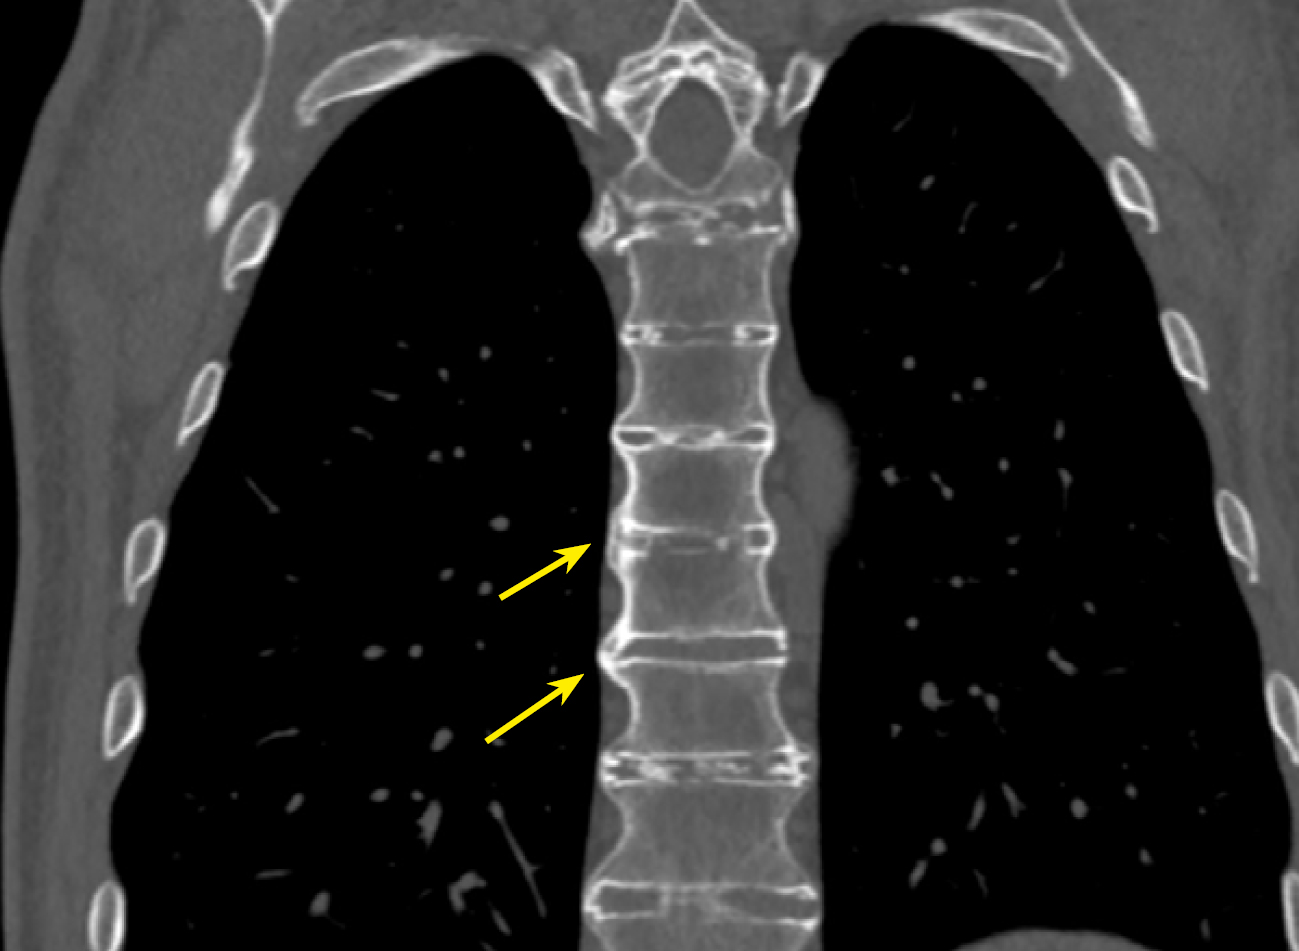

Рисунок 3. МСКТ пациента А. с акромегалией 37 лет, коронарная проекция. ОА плечевого сустава, грубые костные разрастания по контурам головки плечевой кости (стрелка).

Figure 3. MSCT of patient A. with acromegaly, 37 years old, coronal view. OA of the shoulder joint, rough bone growths along the contours of the humeral head (arrow).

В нашем исследовании проведен анализ патологии позвоночника и суставов у пациентов с акромегалией. Спондилоартроз выявлен почти у всех пациентов — 95,9%, чуть реже визуализирован ОА реберно-позвоночных суставов 89,8% и ОА грудино-реберных суставов в 75,9% случаев (табл. 3, рис. 2–5).